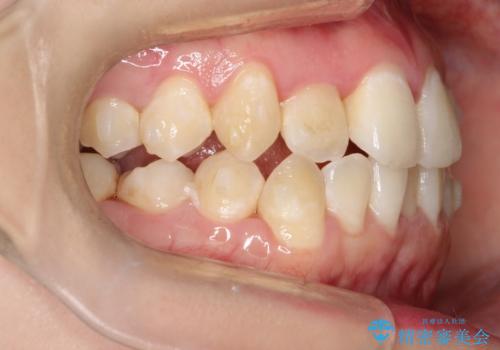

前歯が前後反対にかんでいる インビザラインによる矯正

- 前歯のがたつきを気にされて来院されました。

上顎の前から二番目の歯が内側に入り込んでおり、前後反対にかんでいる状態でした。

歯と歯の間にわずかに隙間を作り並べる計画としました。